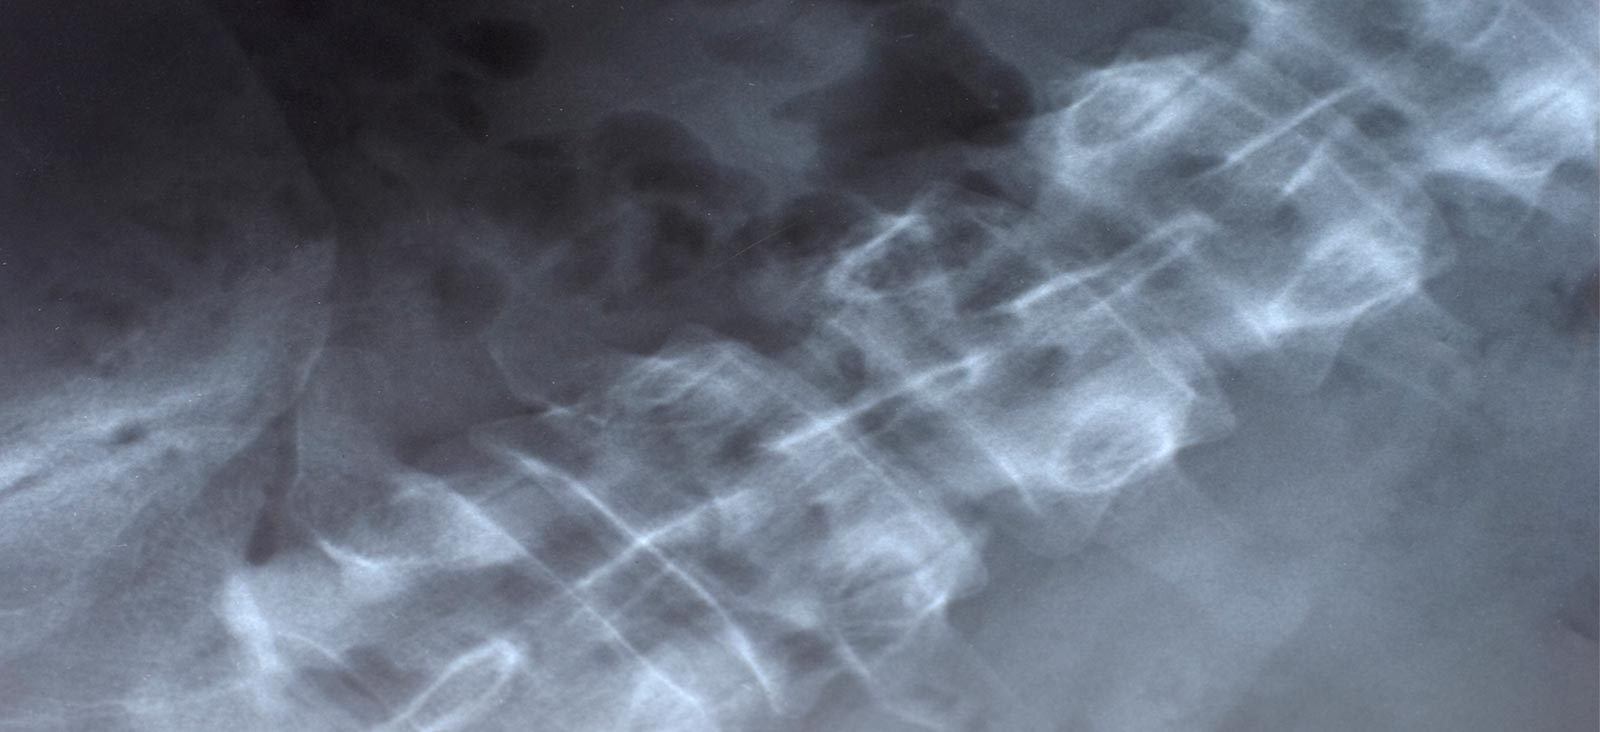

Spinal fractures – broken bones in the back, neck, or spine – vary widely in severity. They also have many causes, including from trauma; conditions, such as osteoporosis, that weaken the bones; tumors, both cancerous and noncancerous; and, rarely, genetic conditions.

If we suspect a spinal fracture, we’ll conduct a physical examination and order spine imaging studies. Spinal fractures are diagnosed with imaging technologies that can include: